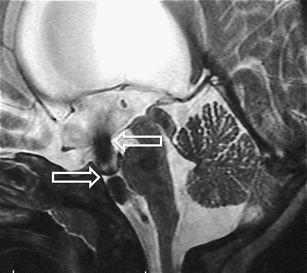

The sylvian aqueduct is the most common site of intraventricular blockage of the cerebro-spinal fluid. Clinical aspects, neuroradiological appearance, and treatment of hydrocephalus secondary to aqueductal stenosis are specific.

The correct interpretation of the modern neuroradiologic techniques may help in selecting adequate treatment between the two main options (third ventriculostomy or shunting). In the last decades, endoscopic third ventriculostomy has become the first-line treatment of aqueductal stenosis; however, some issues, such as the cause of failures in well selected patients, long-term outcome in infant treated with ETV, and effect of persistent ventriculomegaly on neuropsychological developmental, remain unanswered.